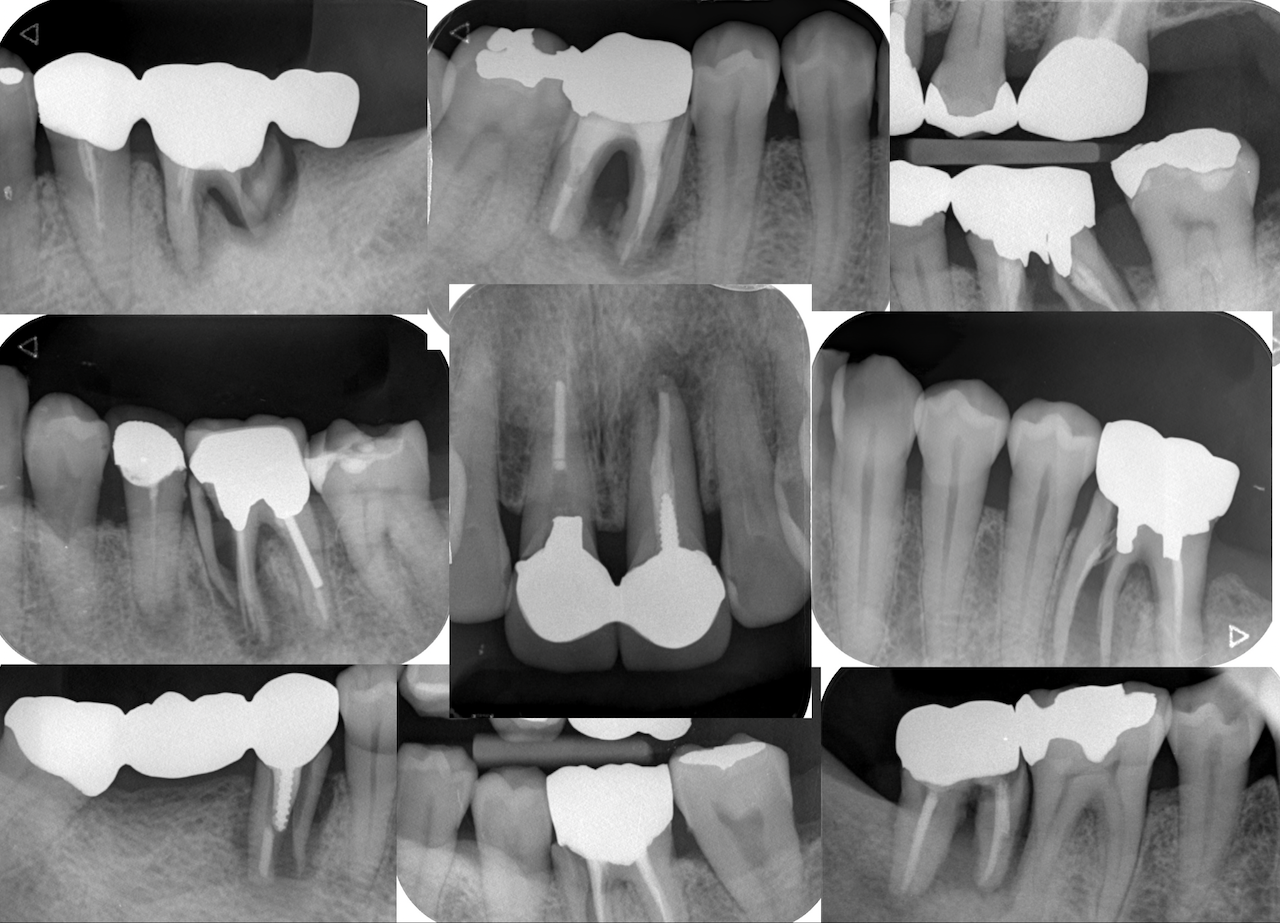

すべての歯牙が歯内療法処置済み歯である。

そして最後にケースを提示した。